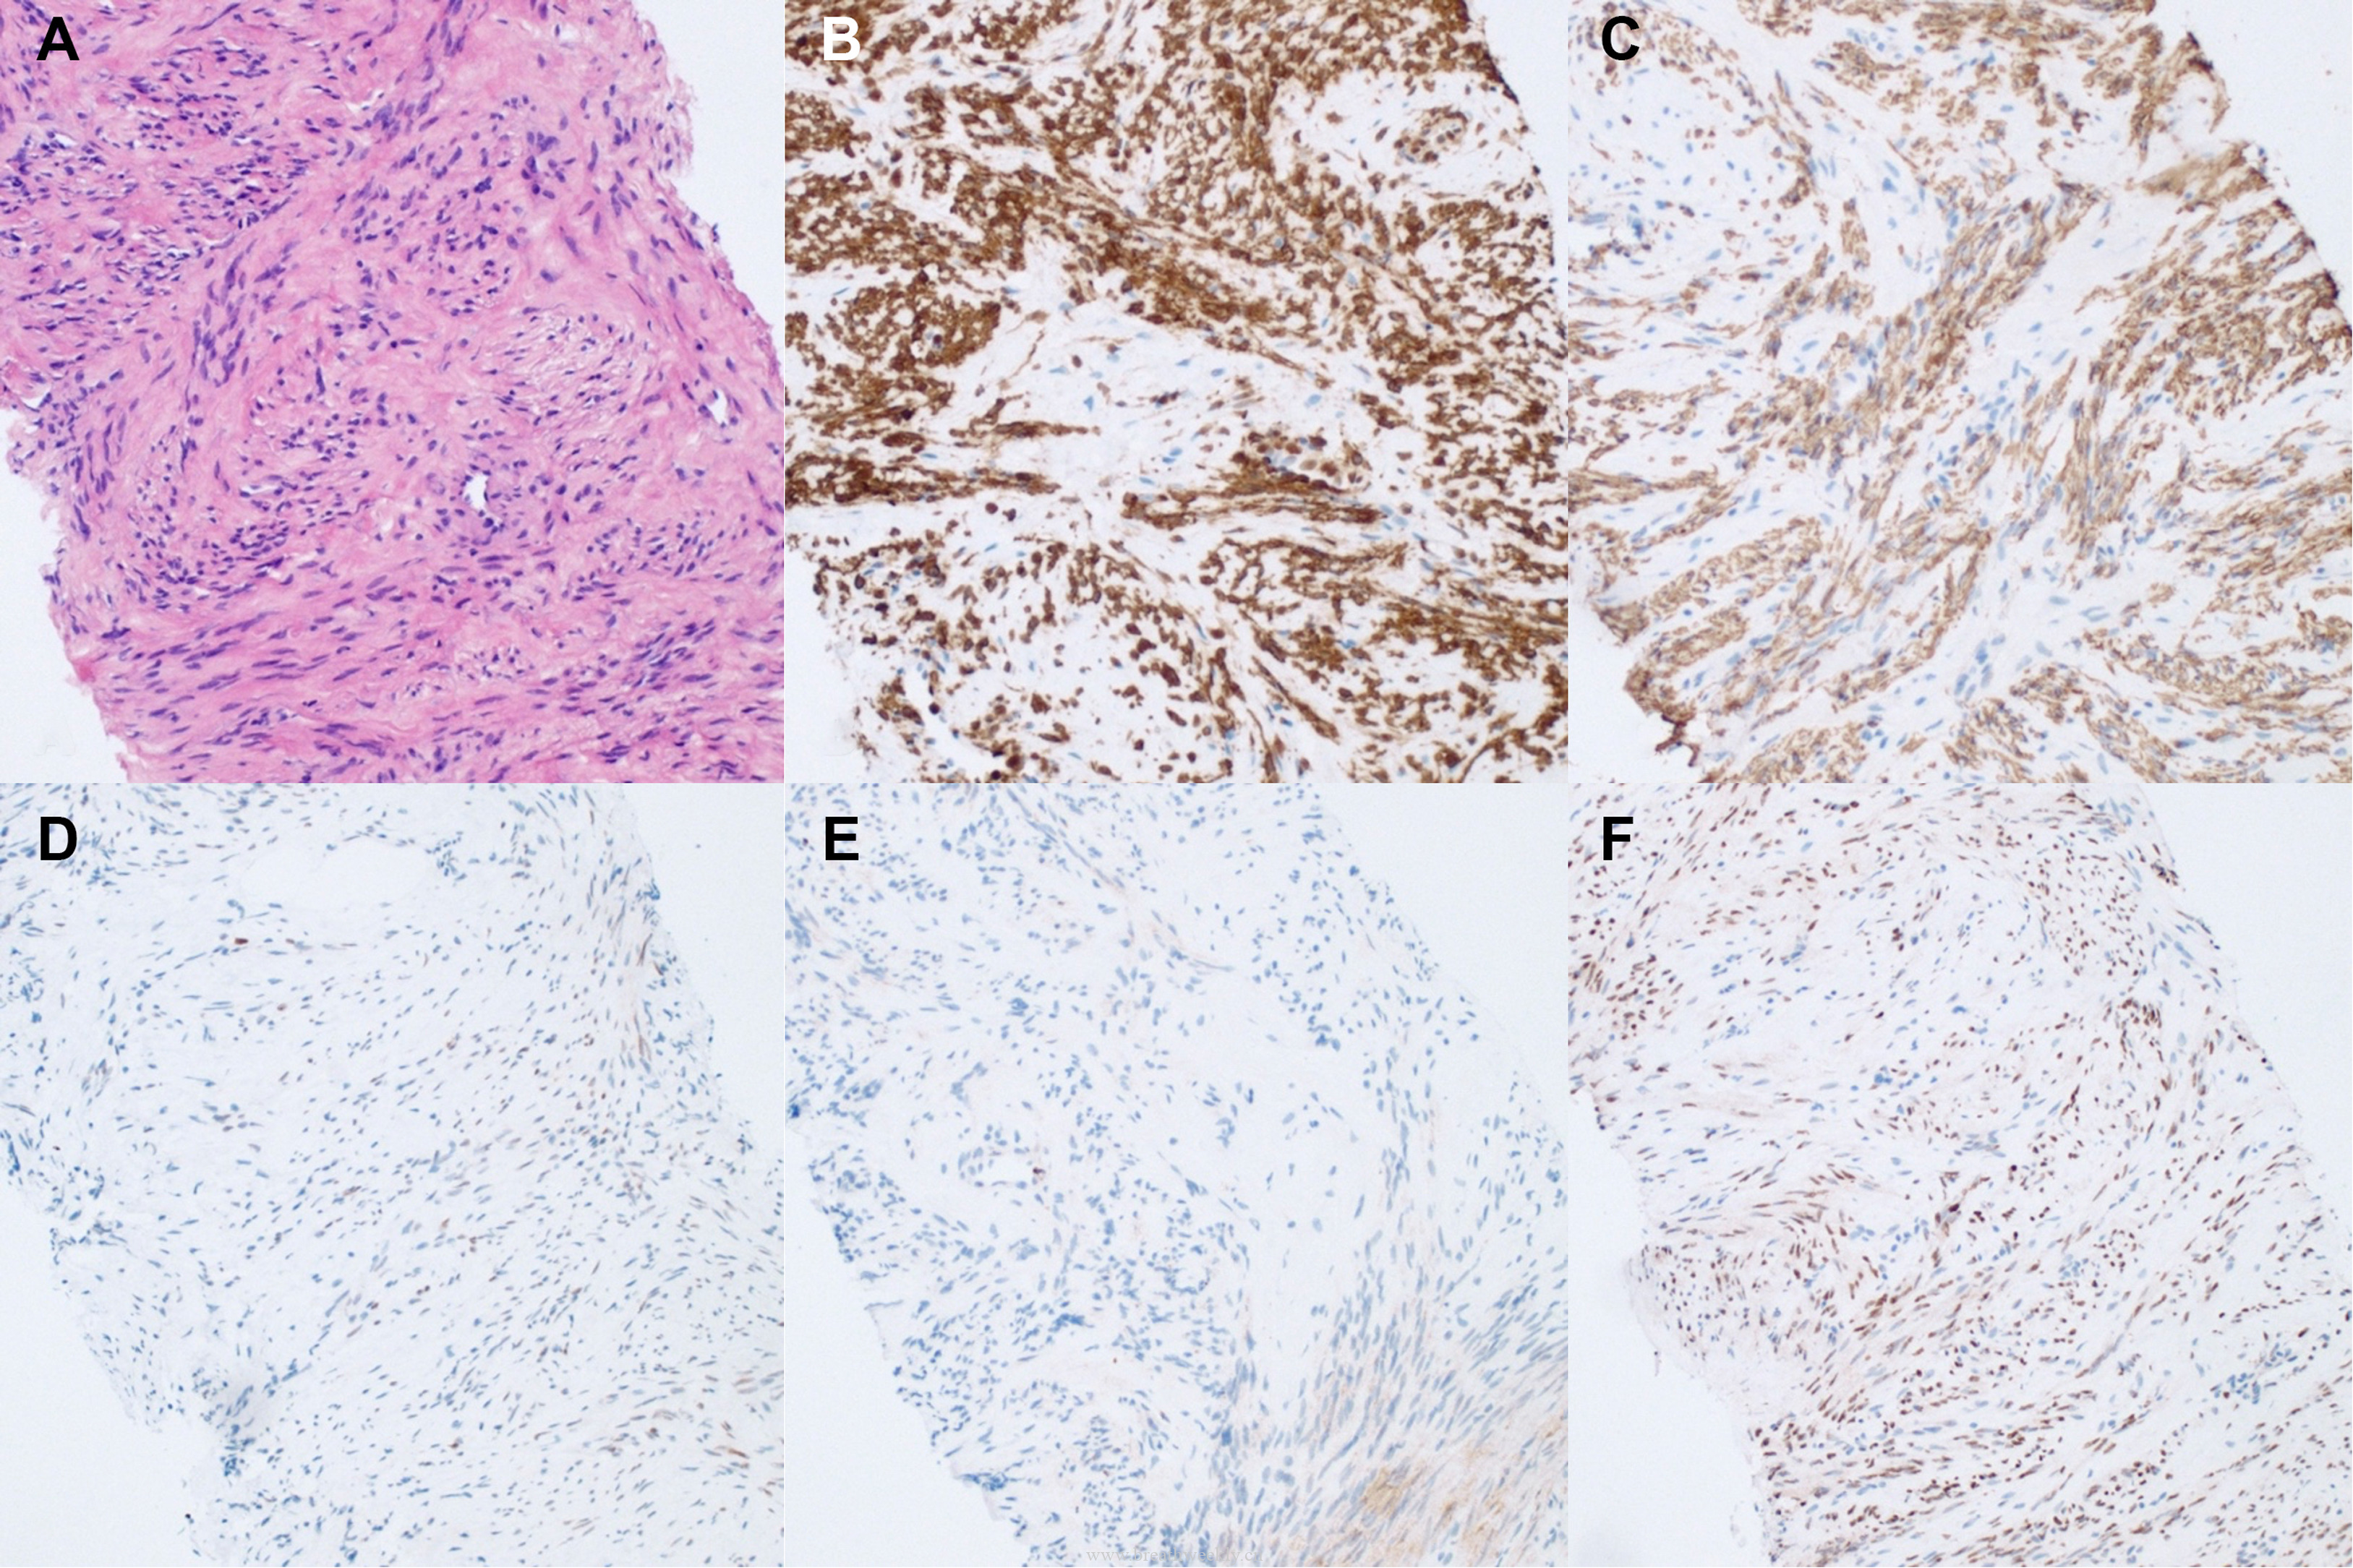

临床过程:因纵隔病灶位置位于甲状腺右叶后下方,术前考虑异位胸腺瘤或异位甲状旁腺腺瘤。CT及超声示无claw sign,排除甲状腺来源。99mTc-Sestamibi显像定位病灶。MG予糖皮质激素及IV免疫球蛋白治疗效果良好;高钙血症予IV补液及cinacalcet治疗。最终行机器人辅助纵隔甲状旁腺腺瘤及胸腺切除术,病理确诊甲状旁腺腺瘤。术后患者恢复良好。

原发性甲状旁腺功能亢进症以高钙血症伴不适当正常或升高PTH为特征。典型表现为肾结石、骨病变(骨炎性纤维囊性变)。本例由单发甲状旁腺腺瘤引起,囊性变性罕见(仅1%-4%)。胚胎发育中,甲状旁腺来自第3、4咽囊,行程较长,故可异位于上纵隔。

本例MG与甲状旁腺腺瘤共存极为罕见,可能为偶发,但两者均为自身免疫性疾病,且胸腺与甲状旁腺有共同胚胎起源,不排除属于自身免疫性多腺体综合征3型(AITD、MG/胸腺瘤及其他内分泌疾病)的可能。

- 胸腺瘤常位于前上纵隔。约4%的胸腺瘤为异位,可发生于颈部、甲状腺、胸膜、肺等部位。约40%的胸腺瘤可出现局灶性囊性变,但广泛囊性变性罕见。胸腺切除术可提供肿瘤学和神经学双重获益。

- 原发性甲状旁腺功能亢进症多为散发,由单发腺瘤引起最常见,20%患者可出现异位。异位甲状旁腺腺瘤约1%-4%可出现囊性变性。手术是根治手段。